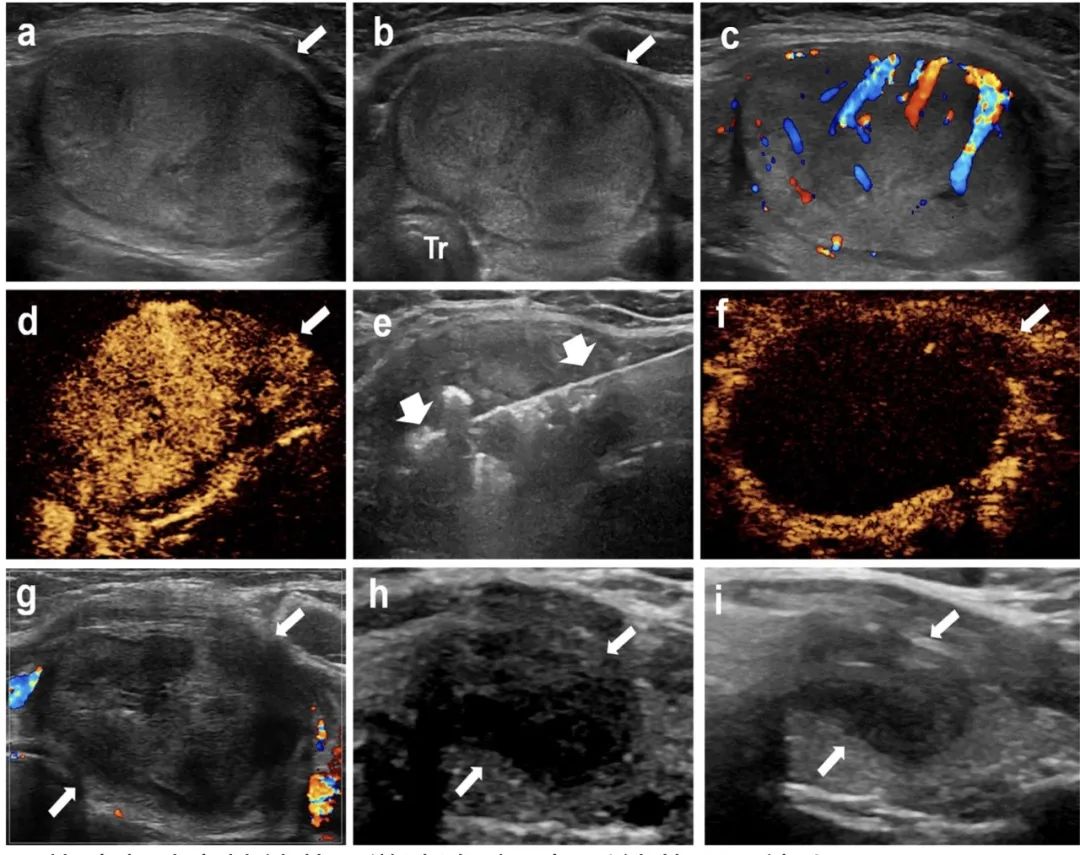

甲狀腺左葉實性結節(jié),微波消融4年后結節(jié)明顯縮小